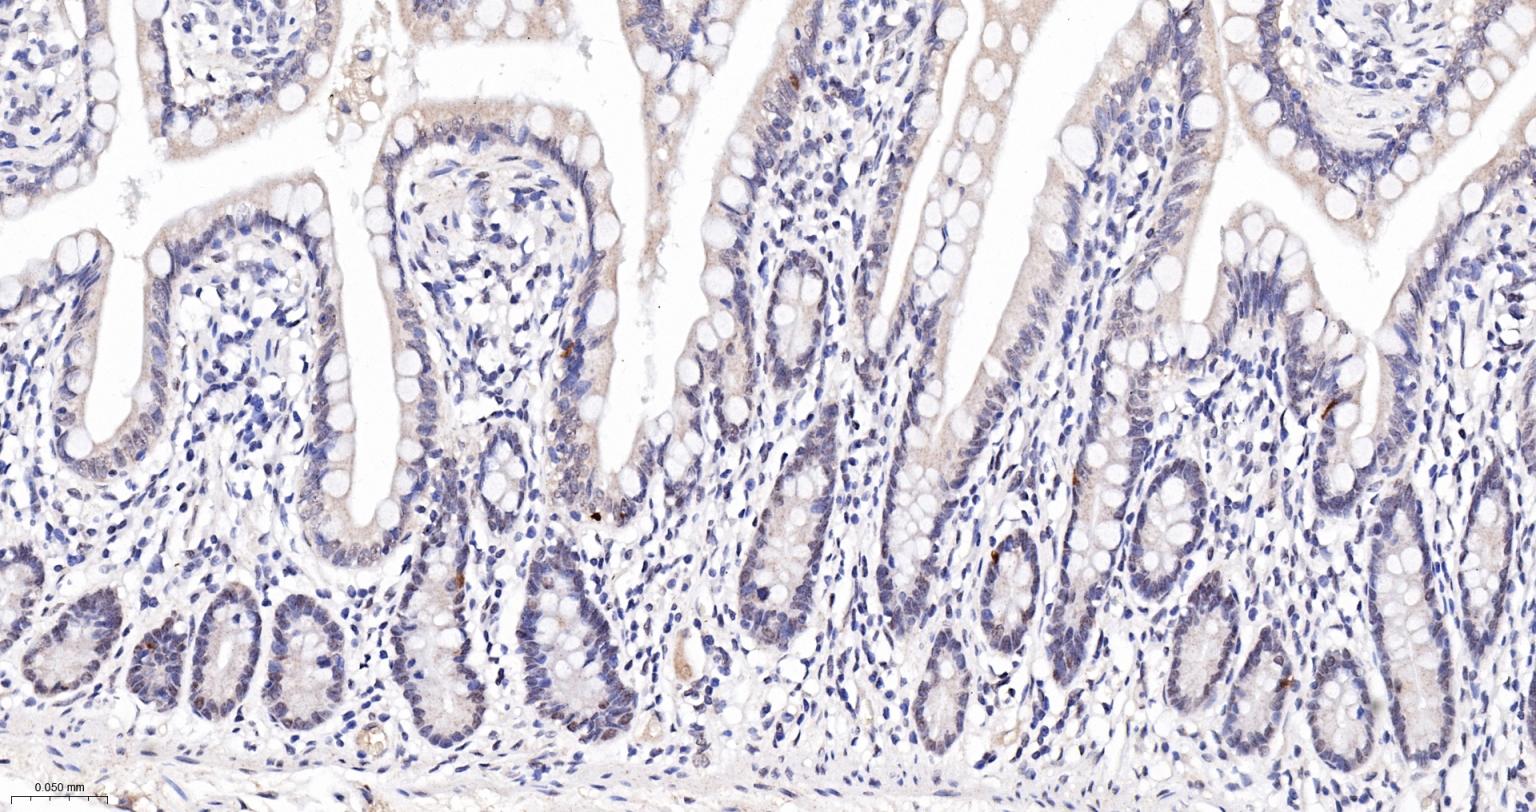

Paraformaldehyde-fixed, paraffin embedded Human Small Intestine; Antigen retrieval by boiling in sodium citrate buffer (pH6.0) for 15 min; The section was incubated with MAD2L1BP Monoclonal Antibody, Unconjugated (bsm-61271R) at 1:200 overnight at 4°C, followed by conjugation to the bs-0295G-HRP and DAB (C-0010) staining.